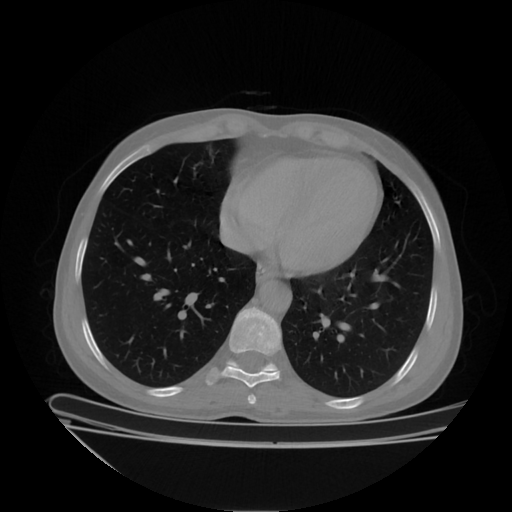

Generated VENOUS CT scan (A→B translation)

Full window (WL 1023.5, WW 4095 β†’ Low βˆ’1024, High +3071)

Actual HU range: [-1024.0, 959.4]

Lung window (WL -600, WW 1500 β†’ Low βˆ’1350, High +150)

Actual HU range: [-1350.0, 150.0]